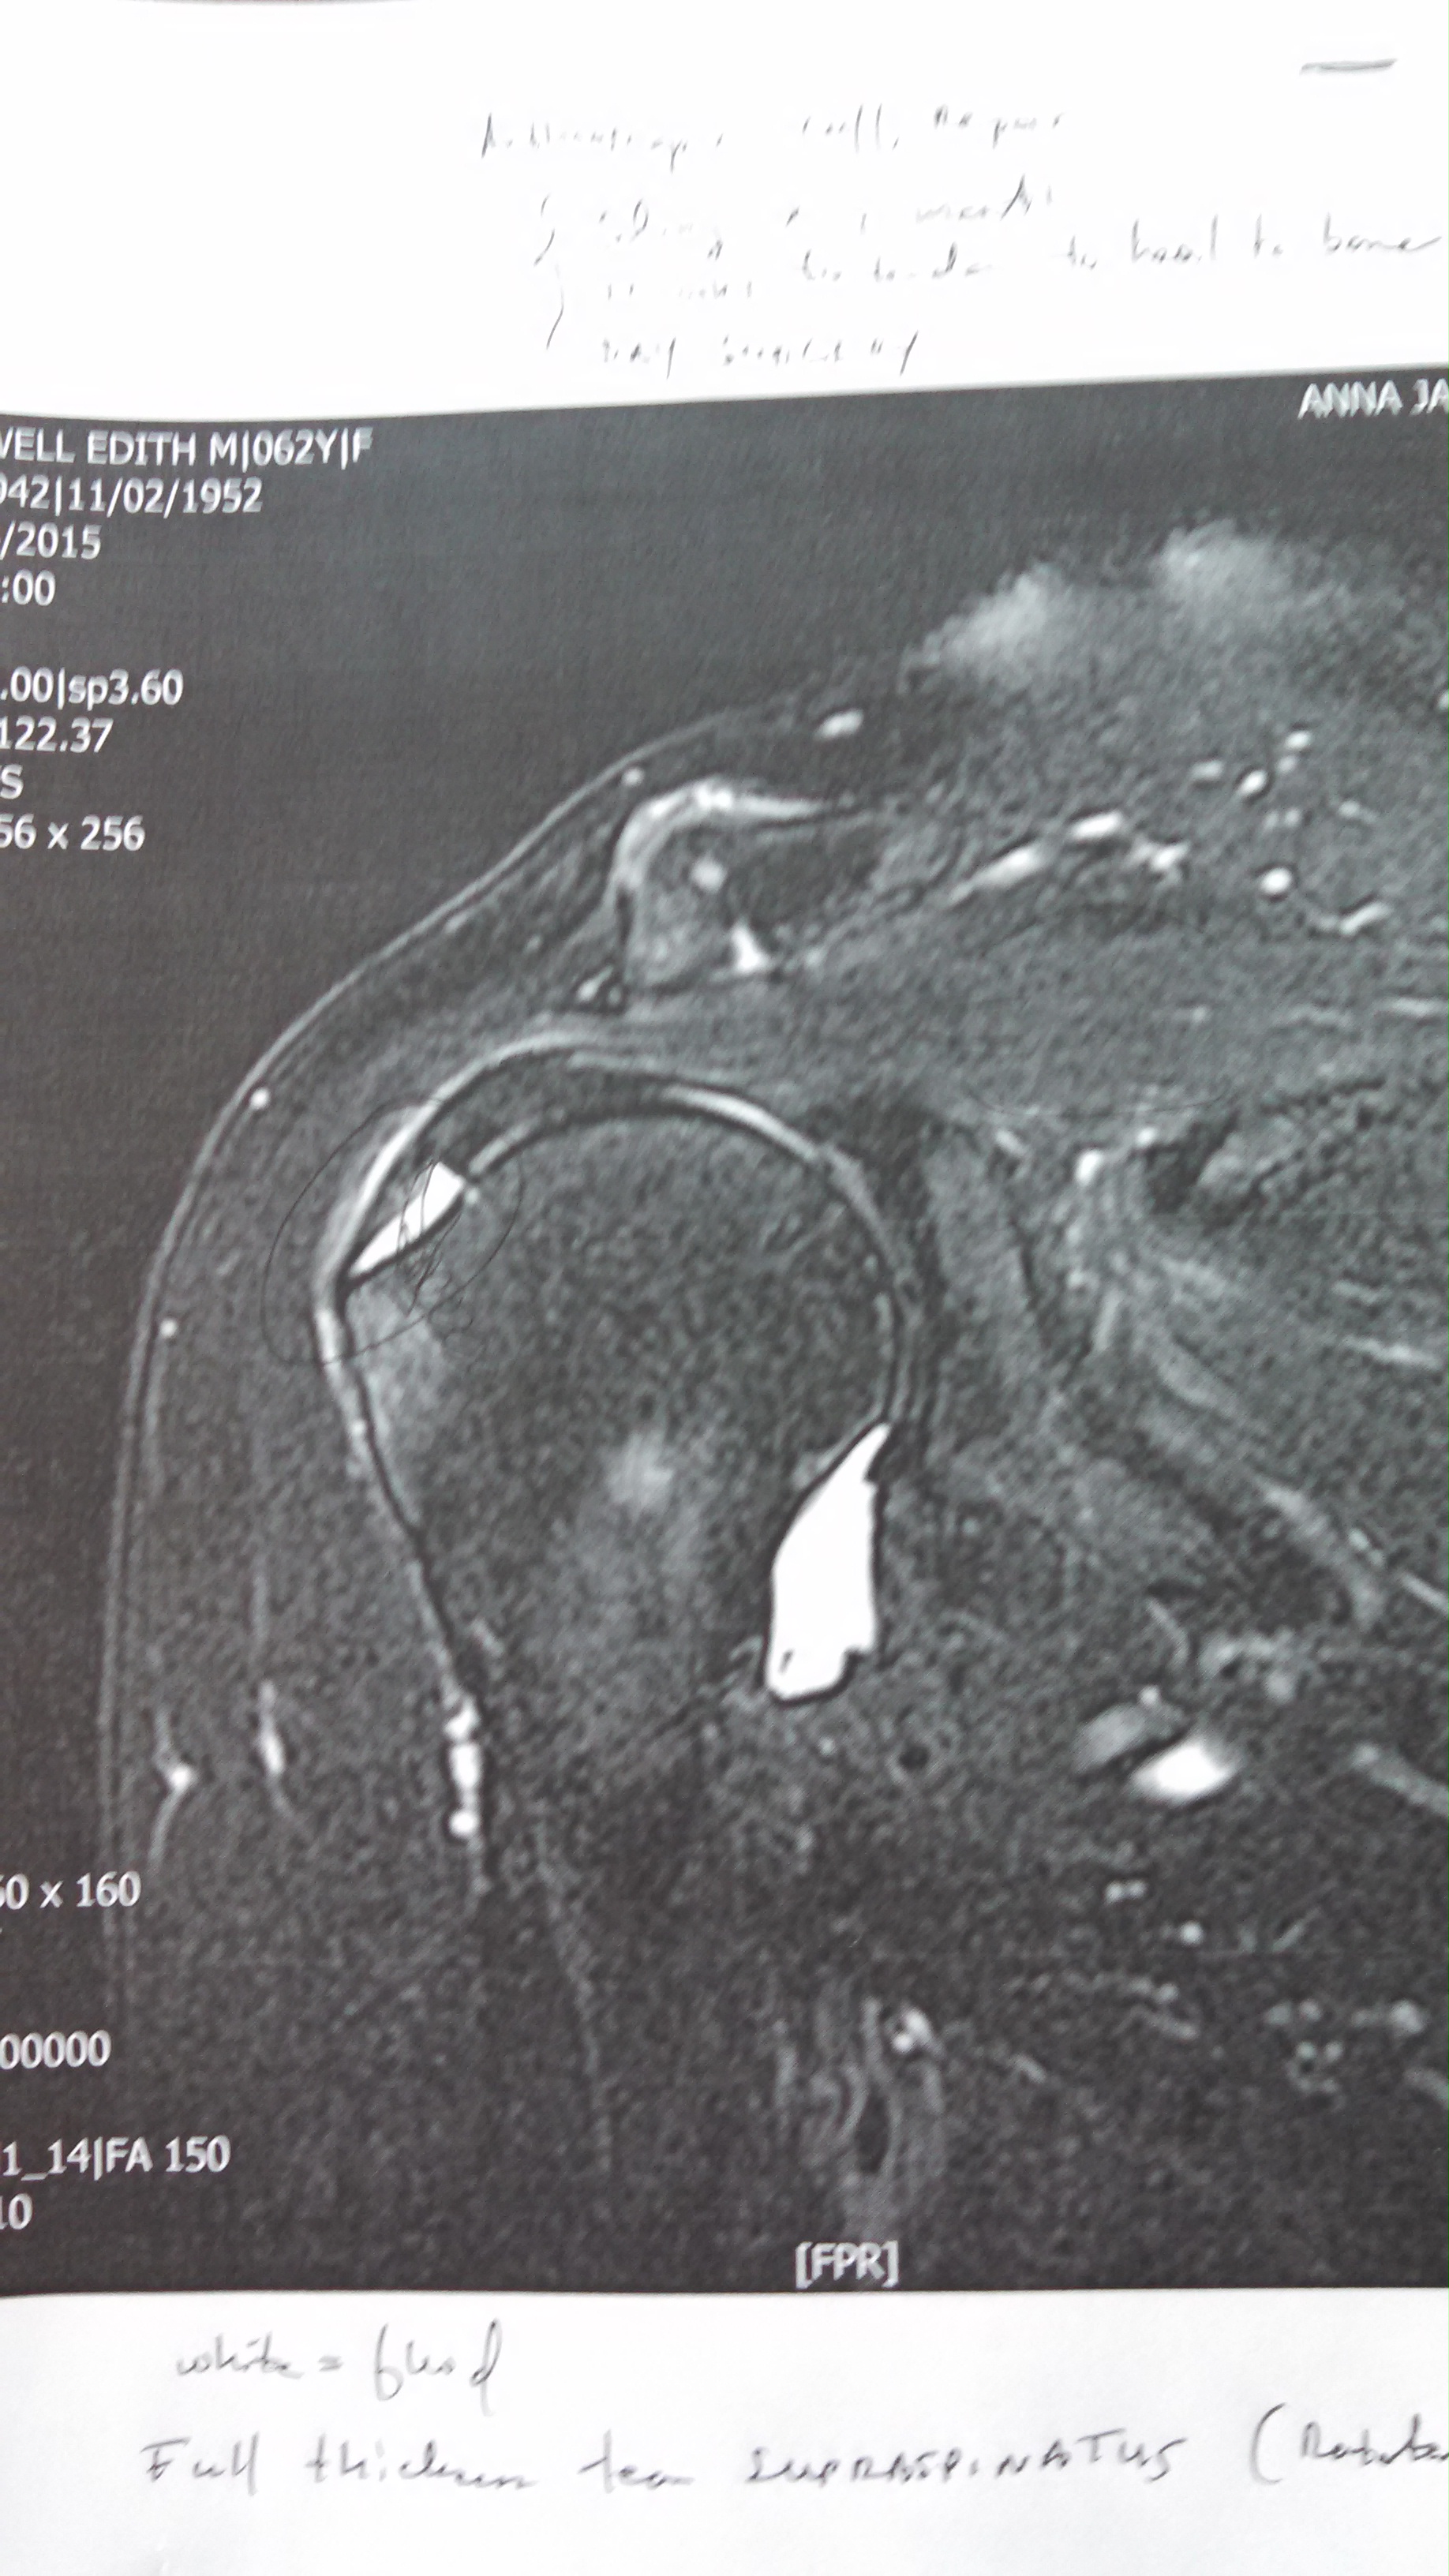

My right shoulder has been hurting for three or four years, and it finally got bad enough for me to get it checked out last fall. After a cortisone injection and a month of physical therapy failed to fix it, my doctor ordered an MRI. Here’s the verdict:

“Full thickness tear of the supraspinatus tendon, with resultant 11 mm tendinous gap.” Which means one of the four tendons in my right rotator cuff has a big honking tear in it. That white pointy shape at ten o’clock is the 11 mm gap. The big white shape at five o’clock is fluid also caused by the tear.

I like Dr. Mattheos and he comes highly recommended by my primary care doc. When Dr. Mattheos was explaining the tear, he wrote everything down for me on the printout of the MRI. I thanked him and he said, “I treat everybody like my dad. He’s from Greece and his English isn’t that good. I tell him, you have to understand what’s happening.” He says he does two shoulder repairs a week, so I know I’m in good hands.